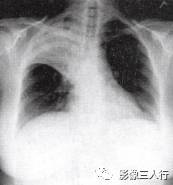

由于实变的肺组织与含气的支气管相衬托,在实变区中可见透明的支气管影即空气 支气管征,临床常见于大叶性肺炎的实变期,包括红色肝样变及灰色肝样变期,表现为密度均匀的致密影内可见透明的支气管影(图1)。这一征象被认为是肺泡炎性病变的有力证据。 医学百科网 | YxBaike.Com

胸部影像常呈肺段或肺叶急性炎性实变。影像实变期表现为密度均匀的致密影,在实变 区中可见空气支气管征。其病理基础是由于广泛的肺泡腔内炎性渗出,肺充气明显减少,使 正常充气的各级支气管与实变的肺泡构成鲜明的对比,形成支气管充气征。见图4至图6。 医学百科网 | YxBaike.Com